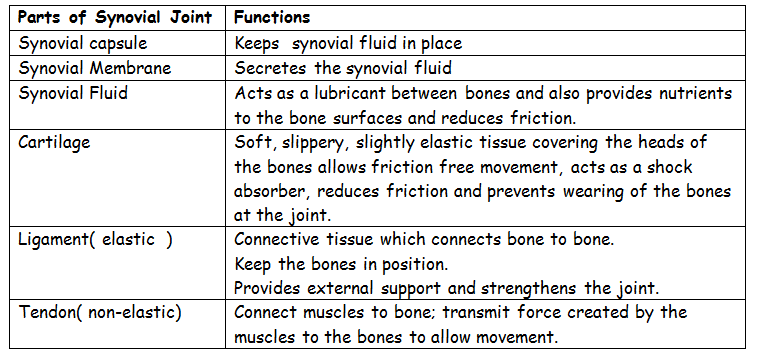

Parts of a joint Functions

Cartilage It serves as a shock absorber when the joint is under stress.

Synovial fluid - It lubricates the joint and allows for free movement.

Capsule - Wraps up and protects the inner delicate parts of the joint.

Ligament - Holds the joining bones in a ball and socket joint together.

Tendon - Holds the joining bones in a hinge joint together.

Parts of a joint Functions

Cartilage It serves as a shock absorber when the joint is under stress.

Synovial fluid - It lubricates the joint and allows for free movement.

Capsule - Wraps up and protects the inner delicate parts of the joint.

Ligament - Holds the joining bones in a ball and socket joint together.

Tendon - Holds the joining bones in a hinge joint together.